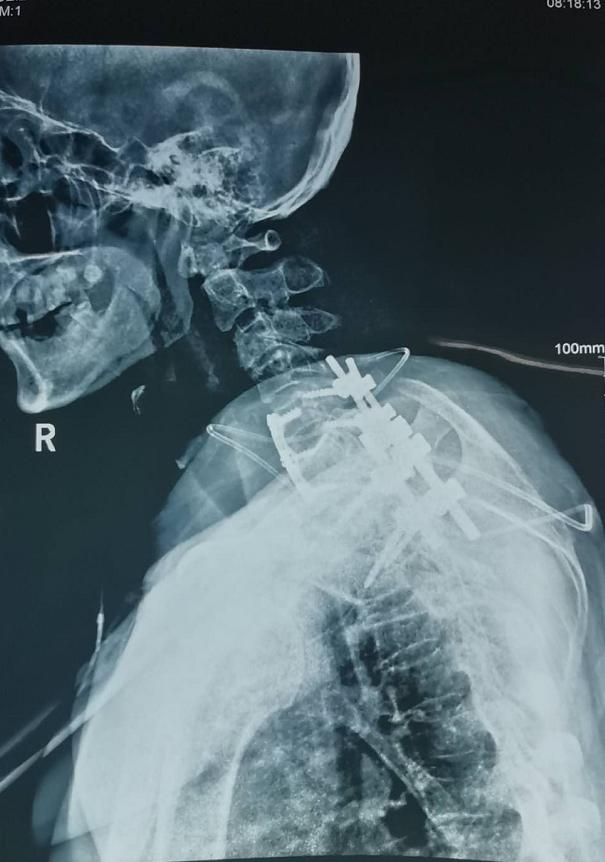

王先生今年64岁,入院时乳头以下全身麻木、不能走路、二便障碍,经核磁及CT检查发现“颈6椎体占位性病变”,且从发病至不能走路只经历约1个月时间,如不能得到及时治疗,患者出现高位截瘫的风险非常高。经市二院骨科医院骨八科主任田晓东(院长助理)及其团队的精心治疗,为患者进行颈胸段前后路联合手术、病灶清除内固定手术,术后一周,王先生感觉麻木消失,能自行下床活动,目前王先生恢复良好。

术后影像

此种颈胸段前后路联合手术,难度较大,辽西地区鲜有开展,锦州二院独立完成此手术,无疑让骨病患者重塑健康信心,给骨病患者带来健康福音。